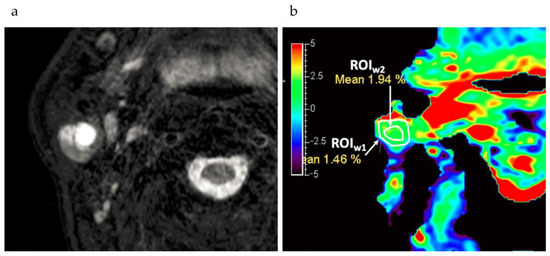

- Evans, V.S.; Torrealdea, F.; Rega, M.; Appayya, M.B.; Latifoltojar, A.; Sidhu, H.; Kim, M.; Kujawa, A.; Punwani, S.; Golay, X.; et al. Optimization and repeatability of multipool chemical exchange saturation transfer MRI of the prostate at 3.0 T. J. Magn. Reson. Imaging 2019, 50, 1238–1250. [Google Scholar] [CrossRef] [PubMed]

- Kim, M.; Torrealdea, F.; Adeleke, S.; Rega, M.; Evans, V.; Beeston, T.; Soteriou, K.; Thust, S.; Kujawa, A.; Okuchi, S.; et al. Challenges in glucoCEST MR body imaging at 3 Tesla. Quant. Imaging Med. Surg. 2019, 9, 1628–1640. [Google Scholar] [CrossRef] [Green Version]